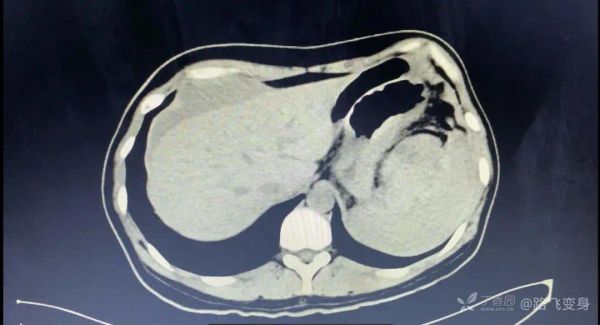

病人出现「休克」症状,没有办法只有准备手术,术前常规行全腹部 CT 检查,如下:

CT 发现明显异常。可以和下面第一次急诊 CT 视频做对比。

这时候你看出问题了吗?猜猜诊断?